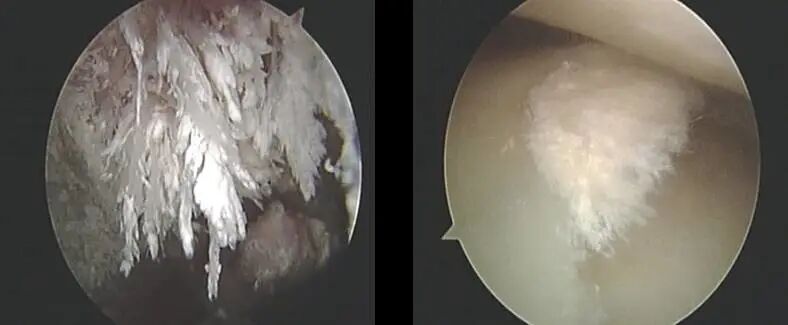

各種關(guān)節(jié)炎的關(guān)節(jié)里面有大量的炎癥因子,痛風(fēng)的關(guān)節(jié)里面有大量的尿酸鹽晶體。

幸運(yùn)的是,這些都是容易被水溶解沖走的。

針刀鏡治療的一個(gè)重要過程就是持續(xù)的使用水流沖洗,將蓄積的炎性組織液排出體外。

例如痛風(fēng)病人,對(duì)關(guān)節(jié)內(nèi)的炎性物質(zhì)和細(xì)小的尿酸鹽結(jié)晶進(jìn)行稀釋、灌洗,使其遠(yuǎn)離病灶,排出體外,緩解關(guān)節(jié)腫痛,達(dá)到“排毒”作用。